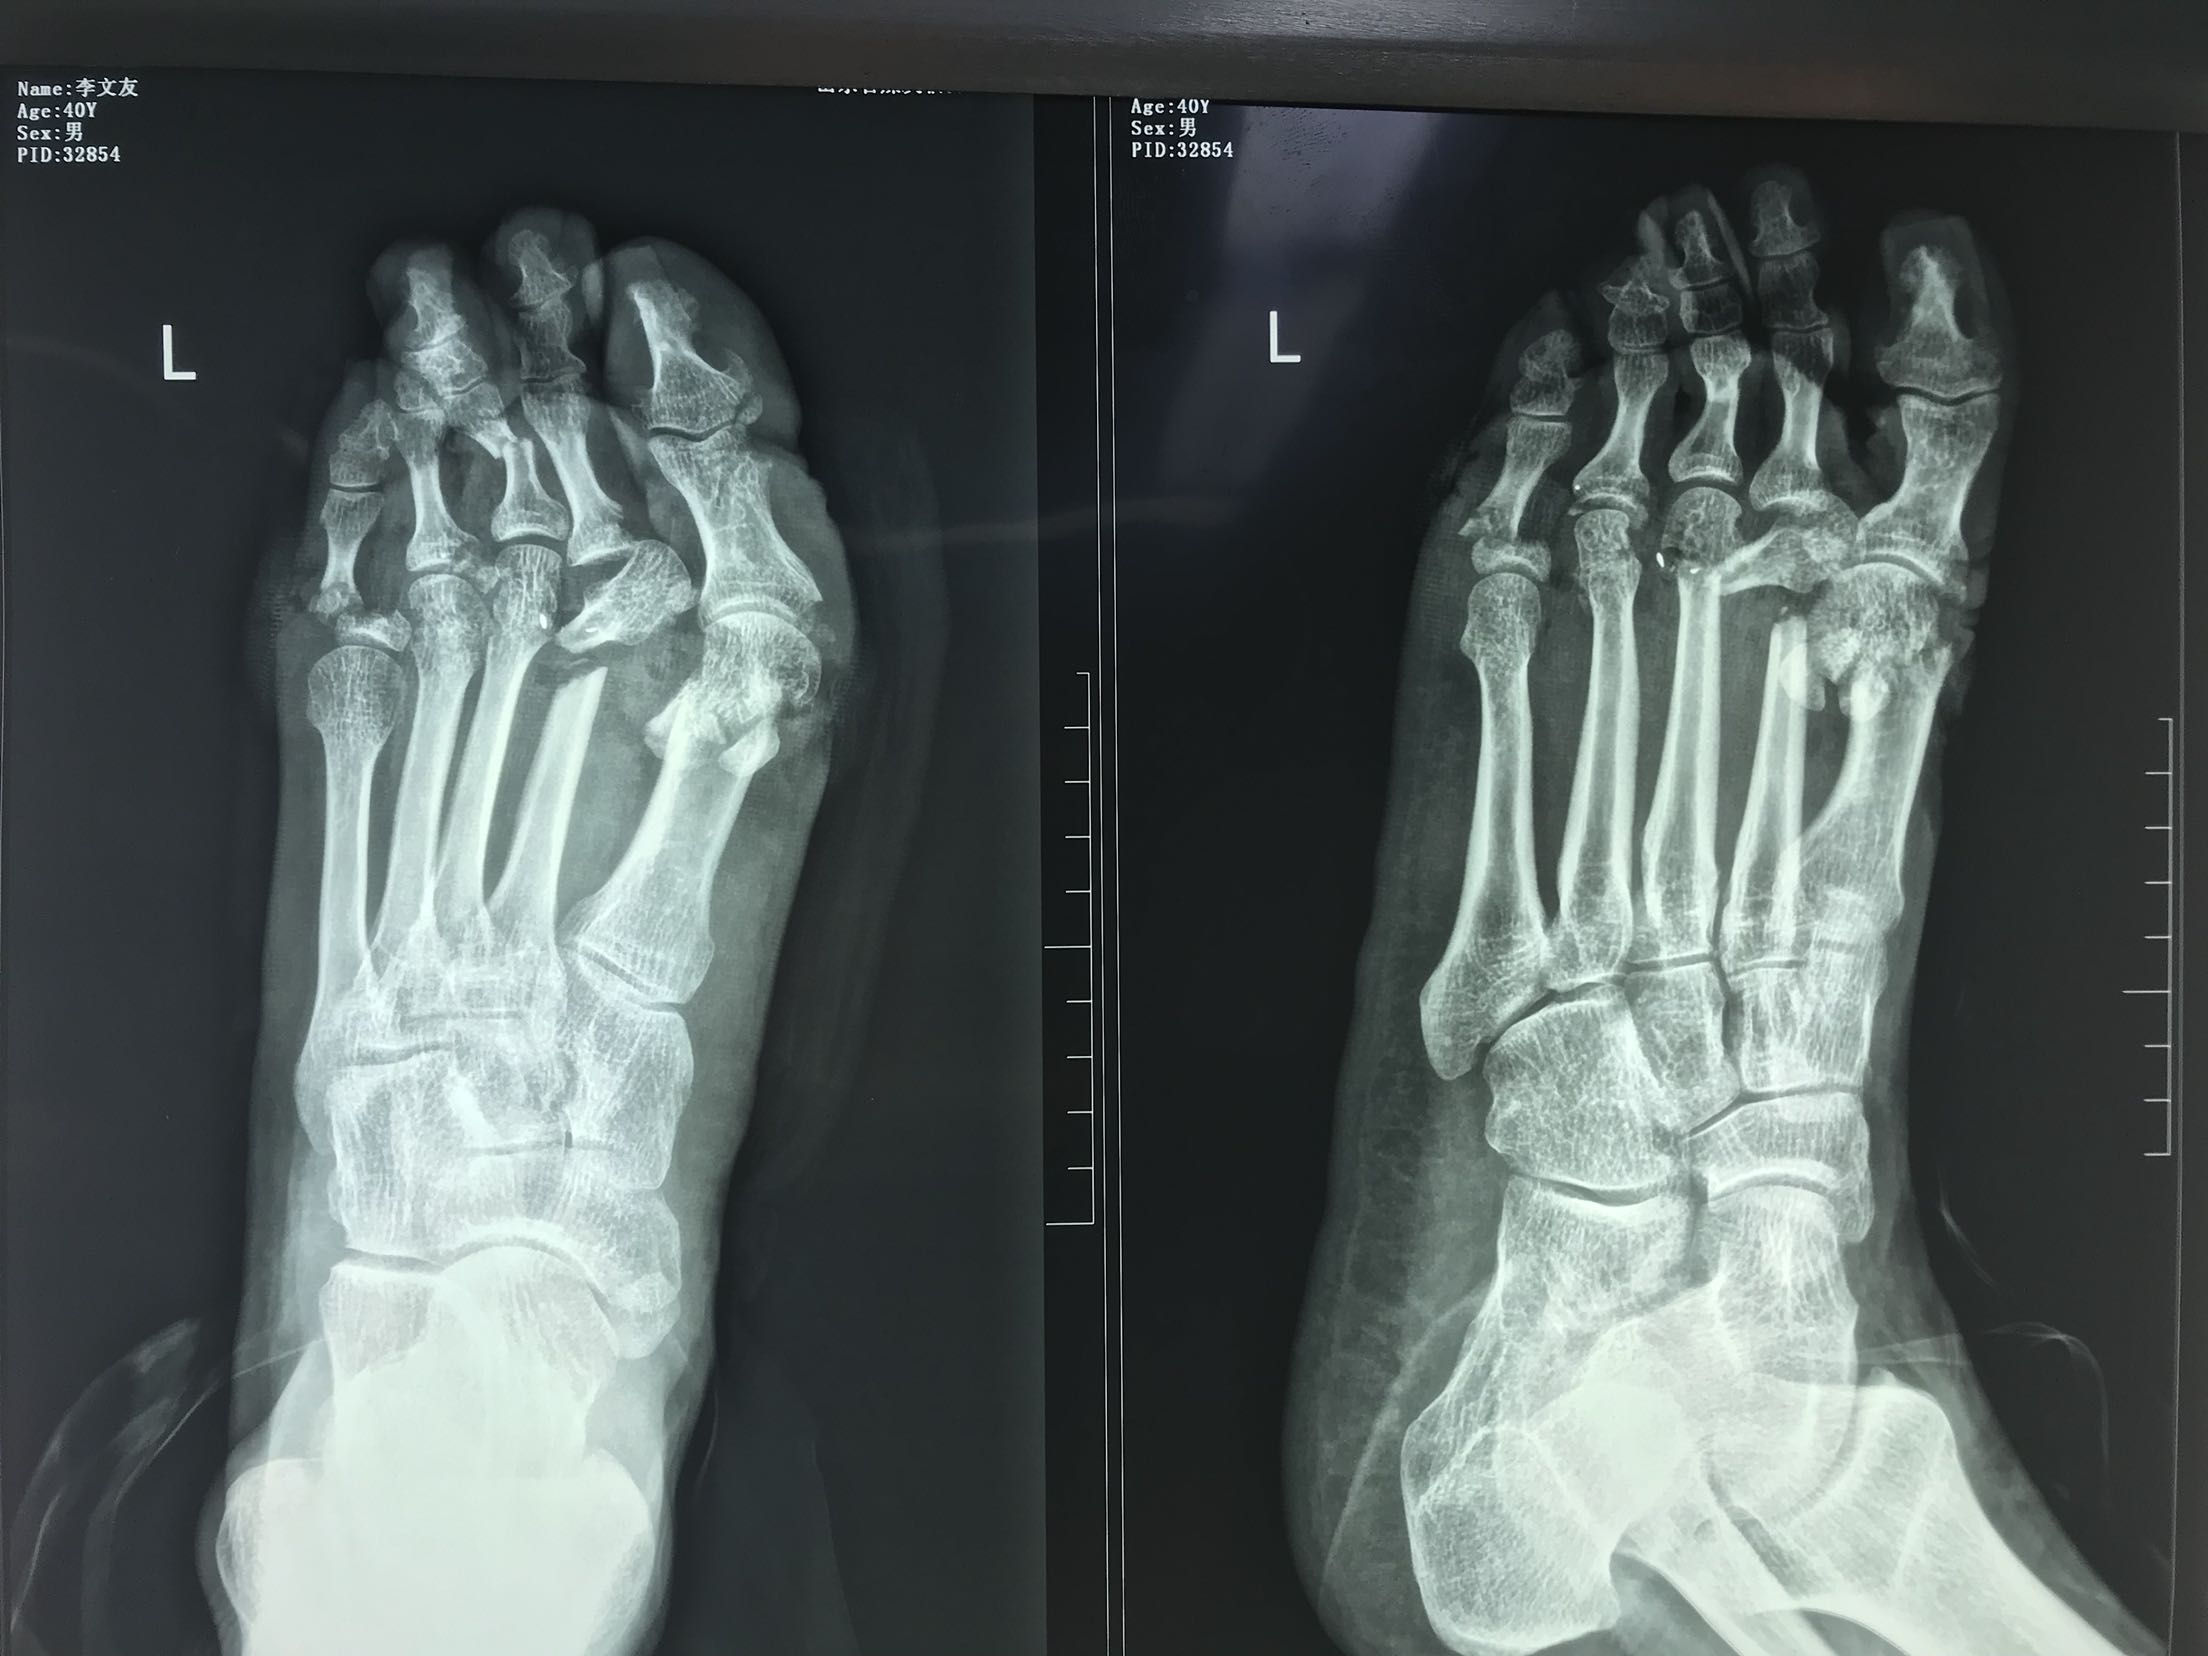

左足跖趾关节部不全离断伤

左足跖趾关节部环形离断创口,足背部一大小约4cm*4cm皮肤缺损创面,创缘不齐,周缘皮肤软组织挫伤严重。趾端颜色苍白,无温度,无血运。患趾主动屈伸活动障碍。余未见明显异常。

左足跖趾关节部不全离断伤。急诊行手术治疗。术中见足背动脉,趾动脉断裂,远端肢体无血运。行清创,骨折复位克氏针内固定,肌腱,血管探查修复,vsd负压吸引术。

术后一个月,第二趾坏死,行截趾术,足背部缺损创面行取皮植皮,大部分成活。